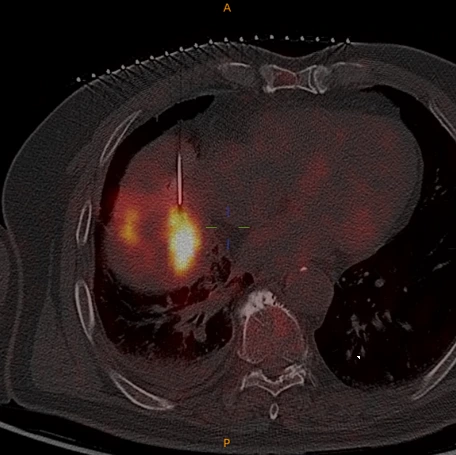

PET/CT,中文全称为正电子发射断层显像/X线计算机体层成像仪,是一种将功能代谢显像(PET)与解剖结构显像(CT)两种先进影像技术有机融合的新型医学影像设备。通过揭示人体内部的代谢与功能状态,为多种疾病,特别是肿瘤的精准诊疗提供了至关重要的信息。

肿瘤微创的核心是采用先进的影像设备进行引导,从最初的X机到超声、CT乃至MRI,我们一直在探索新的影像设备对疾病治疗早期诊断和精准定位。PET/CT在微创领域的应用,标志的肿瘤微创进入分子影像引导的全新领域,最终实现患者获益。

肿瘤微创治疗之所以微创就是对病灶实施精确打击,PET/CT好比相控阵雷达,可以清晰分辨异常和正常组织

PET/CT在融合CT图像后可以完成术中增强扫描,避开危险血管